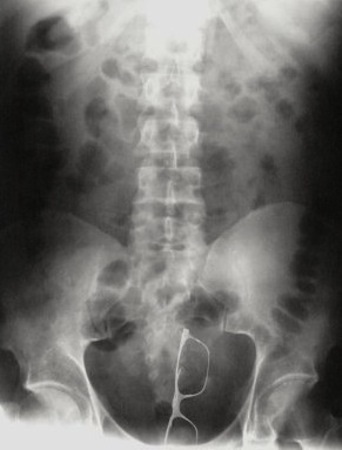

แว่นตาเก๋ ๆ

กุญแจ